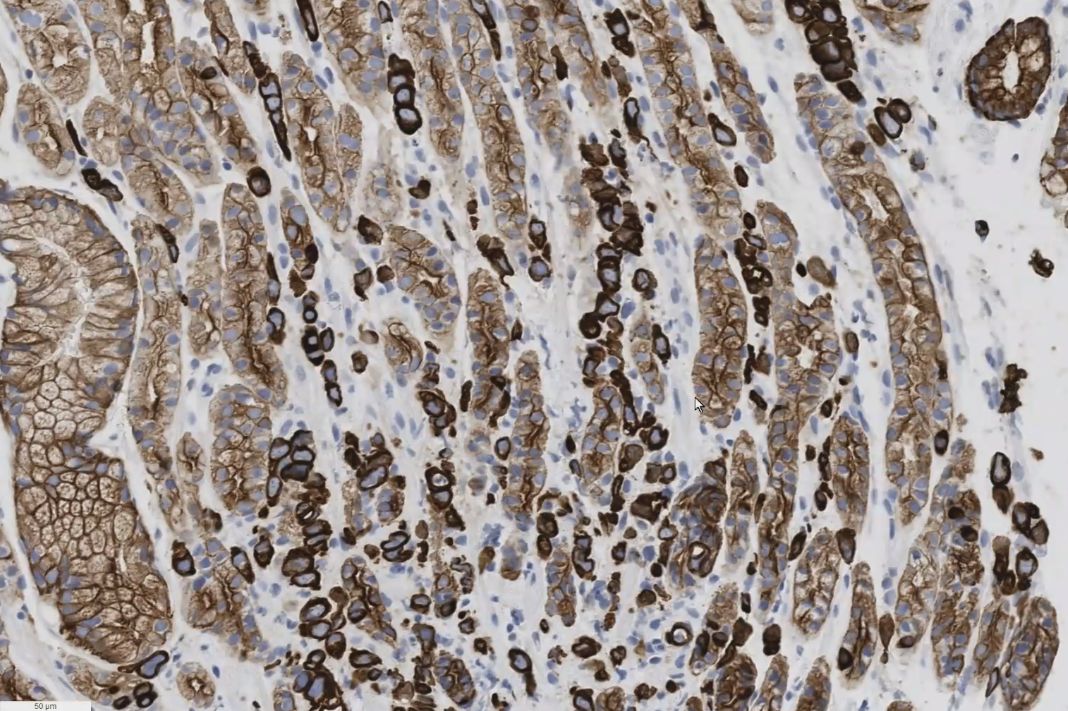

| Morphologie | Zwischen den Mucosa-Drüsen sieht man kleine stark an gefärbte, in Reihen angeordnete Tumorzellen. . | ||||||||||||||||||||||||||||||||